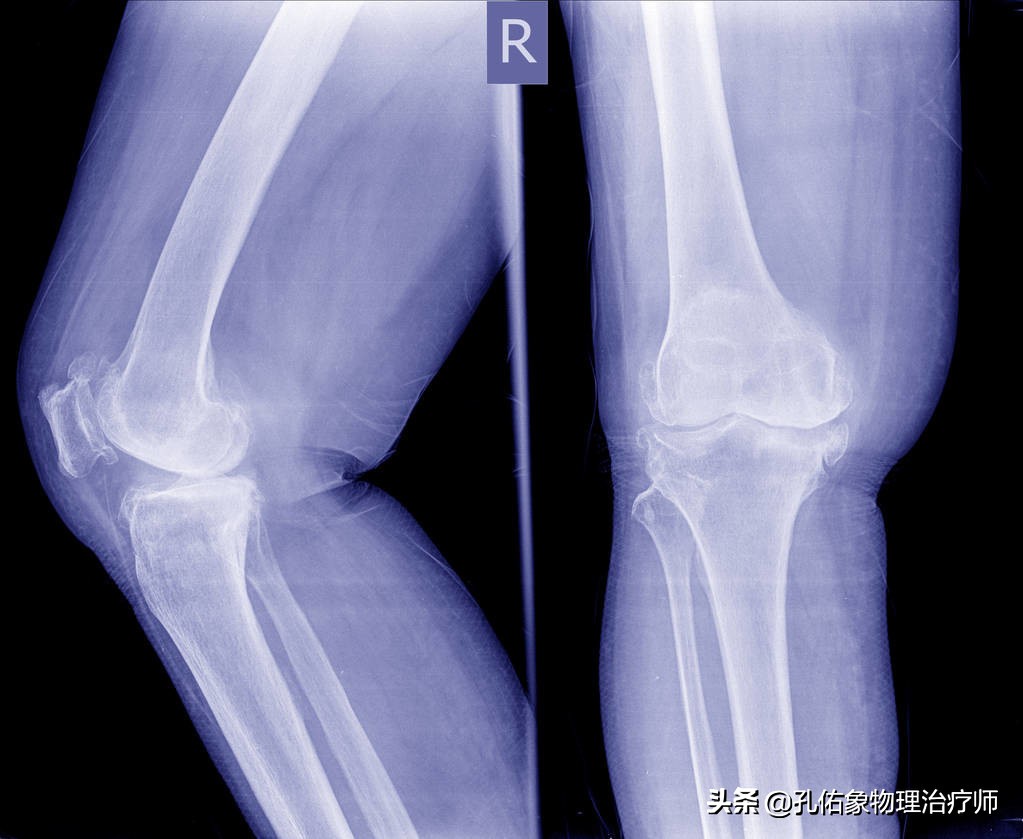

我们往往通过以上四个特殊检查就可以发现膝痛是不是膝盖骨的软骨软化所致?当然了,也可以去拍一张膝关节的正侧位片看看,一般早期疼痛往往在片子上也看不出啥问题,此时需要拍特殊体位的。

- 拍X片(轴位片)

一般在医院里边,很多医生也不会让患者去拍轴位片,都喜欢去拍正侧位片。但是对于膝痛早期的人而言,在下蹲过程中出现疼痛时的角度去拍轴位片,会发觉挺有意思的,膝盖骨是外移的,并没有在正常的髁间窝里边,这就是典型的膝盖骨软骨软化的表现。

这样的膝痛,在早期通过片子是很难发现的,所以你无论是做啥治疗,效果都不好。只有找到病因后,从根本的力学入手治疗才是上策。若是不及时治疗,使膝盖骨一直处于不正确的轨迹里面运动,最终膝痛厉害,活动受限,拍X正侧位片会显示膝盖骨边缘骨质增生、骨硬化改变及粗糙不平,膝盖骨关节间隙狭窄。